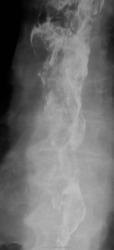

Глядя на картинки, вспомнила пациента с инфильтративной формой злокачественной лимфомы в желудке. А что в клинике? Возраст? Еще подумалось о болезни Крона, но сомневаюсь. Непаханое поле для эндоскопистов (биопсию имею в виду).

Возраст преклонный, сильно похудел, твердая пища не проходит...

Да, для эндоскопистов работа. Изменения пищевода могут быть и функционального характера. Но с учётом возраста думается о плохом. Похоже в ДПК есть дивертикул. Заброс бария в трахею

Добрый вечер. Контраст в трахею попал через свищ  или пациент поперхнулся во время исследования?

Пациент выпил всего два глотка, все время подкашливал.

Часть желудка в горизонтальном положении вышла за купол диафрагмы?

Хмм, изменения в пищеводе по-всякому органические, скорее всего рак.. Только вот что с желудком? Почему-то его так скрутило.., в анамнезе есть язвенная болезнь, может быть улиткообразная деформация?

зы. Похоже, что дно желудка тоже вовлечено..

Еще приходит мысль о бульбарном синдроме, для рака такая протяженность, по-моему, маловероятна.

Пациенту произведена ФГДС, диагностирован рак пищевода...,